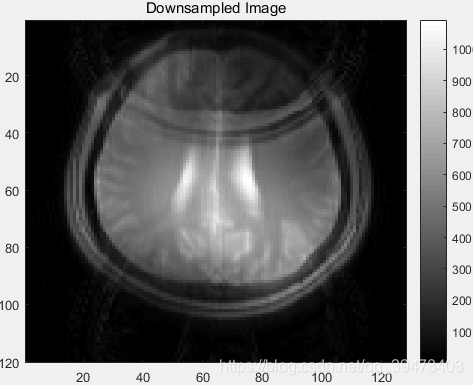

6. 欠采样 k 空间数据 IFFT 转换到图像域并显示

dsBrainCoils 为 R = 2 倍欠采样 k 空间 复数值数据 的 downSampleKspace 图像域 MR 图像 (Nc = 5 个线圈各自的都叠在一起),size = 120×128×5,type = complex double

dsImage 是通过 平方和根 (root-sum-of-square) 方法 组合 所有线圈各自的欠采样 MR 复数值图像数据 dsBrainCoils 而重建的 总体欠采样 MR 实数值图像,size = 120×128,type = double

dsBrainCoils = ifftshift(ifft2(fftshift(downSampledKspace))); % 120×128×5 complex double

dsImage = rsos(dsBrainCoils); % 120×128 double然后,显示总体 R = 2 倍欠采样 MR 图像:

figure;

title('Downsampled Image');